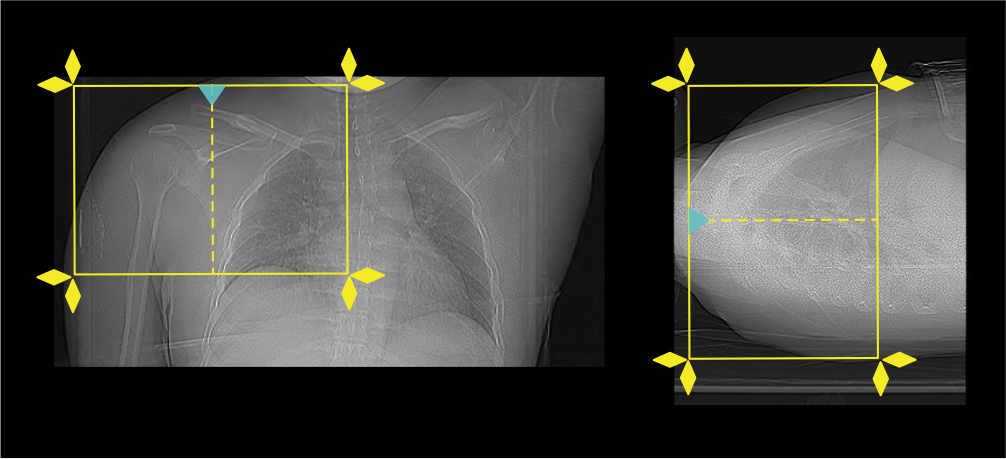

- Set the scout start point at the nipple level and scan direction into the gantry.

Scan planning

- Plan the scan slab to cover from the acromioclavicular joint (ac joint) to inferior angle of the scapula.

- Reduce the field of view (FOV) as appropriate to include scapula, clavicle and humerus.